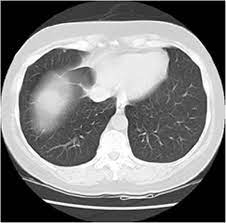

Can You Detect Lung Cancer With Ct Scan - Detection Of Early Stages Of Lung Cancer Based On Imaging A Download Scientific Diagram - Your doctor might use imaging tests to look for unusual growths inside your body that might be cancer.. It can also show whether the cancer has spread outside the lung. It gives detailed information about your cancer. Ct scans of the chest are used to find lung nodules or other chest pathology. Therefore, ct scans can lead to a false negative this can negatively impact your ability to get any treatment at all If cancer is diagnosed, other tests will be performed to stage and grade the tumor so that the appropriate treatment can be delivered.

Google Shows How Ai Might Detect Lung Cancer Faster And More Reliably Mit Technology Review from wp.technologyreview.com Also, this imaging technique can show masses that might have developed as a result of lung cancer spread. But since this test can miss early cancers, additional testing is needed to confirm (or rule out) a lung cancer diagnosis. On the other hand, patients who've had surgeries related to their lungs or lung cancer are advised to take more scans than regular smokers. If the test finds cancer, treatment can start early. It can also show whether the cancer has spread outside the lung. While it might seem obvious to assume that finding small tumors reduces one's likelihood of dying from lung cancer , this is incorrect. Your doctor might use imaging tests to look for unusual growths inside your body that might be cancer. Doctors can use a ct scan to look for lung cancer.

But the test is not helpful for light smokers or people who quit smoking more than 15 years ago. Early detection of lung cancer means more treatment options an excellent tool for people at high risk for lung cancer the scan is quick, painless and noninvasive ct imaging is detailed and accurate and can reveal the smallest of abnormalities The scan looks at your lungs and other parts of your chest. Ct is highly accurate for lung cancer detection. Nevertheless, lung cancer can also be overlooked on computed tomography (ct) scans, regardless of the context, either if a clinical or radiologic suspect exists or for other reasons. A ct scan test can also be used to look for the spread of lung cancer in the adrenal. If you are at higher risk, talk to your doctor about getting screened. The smallest recesses of the chest can be clearly seen. It can also show the size, shape, and position of any lung tumors and can help find enlarged lymph nodes that might contain cancer that has spread. Therefore, ct scans can lead to a false negative this can negatively impact your ability to get any treatment at all Ct scans of the chest are used to find lung nodules or other chest pathology. Alternatively, you should take lung ct scans if you are concerned or if you show any symptoms. It can also look at your liver and adrenal glands.

The scan looks at your lungs and other parts of your chest. Lung cancer screening carries several risks, such as: It can also show whether the cancer has spread outside the lung. It is used to look for early signs of lung cancer. 234 views answered >2 years ago A computer then combines these images into a detailed picture of your lungs. A ct scan can detect potential cancer in a lung. Alternatively, you should take lung ct scans if you are concerned or if you show any symptoms. Are you preparing to have this procedure soon? If the test finds cancer, treatment can start early. If cancer is diagnosed, other tests will be performed to stage and grade the tumor so that the appropriate treatment can be delivered. If you're still concerned about radiation from a ct scan, you can always get a second opinion. Lung biopsy, involving the extraction of suspicious tissues by needle or other methods, is ordered if a ct scan suggests cancer.